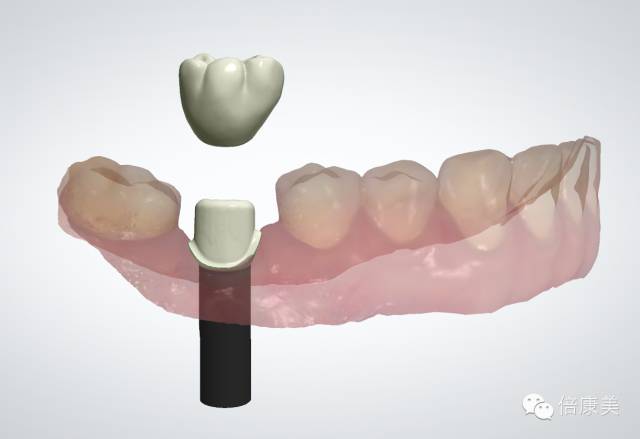

一次扫描即刻获取完整口内种植三维信息

通过口扫获取种植模型,患者可以一次性完成个性化基台和修复冠,缩短修复时间